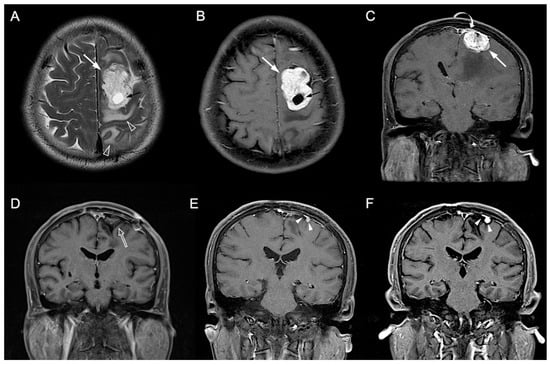

3.1. Clinical and Imaging Findings